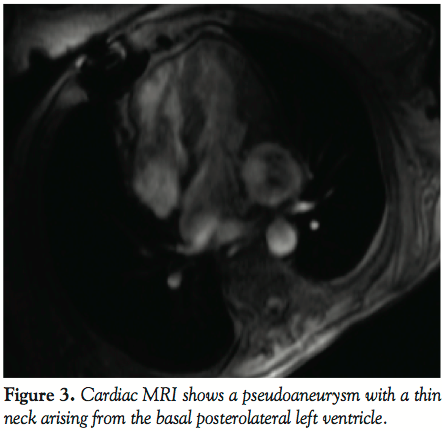

patent bypass grafts and normal pressures on right heart catheterization. Chest CT showed a poorly defined aneurysm in the left side of the heart. Transthoracic and transesophageal echocardiograms revealed a 5 cm LV pseudoaneurysm (Figures 1 and 2). Cardiac MRI showed a 4.2 x 4.3 x 5.8 cm cavitary lesion adjacent to the posterolateral wall of the left ventricle and a small tract from the LV cavity to the cavity (Figure 3). Flow turbulence was noted across this tract. She was referred to cardiothoracic surgery for surgical repair of the pseudoaneurysm. Given the patient’s comorbidities including significant recurrent problems with wound healing, and after careful discussions of risks, benefits, and alternatives, we referred the patient for percutaneous closure of the pseudoaneurysm.